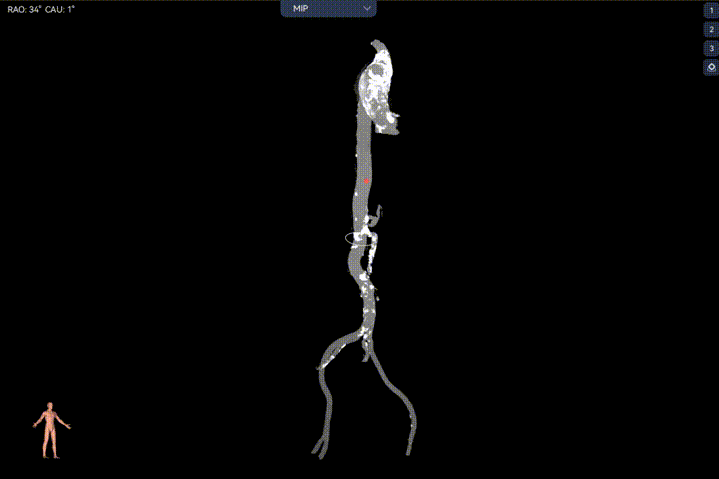

外周双侧入路无明显迂曲、直径可容纳20F大鞘通过,双侧中分叉,穿刺需注意。主动脉弓角弓距可,髂总动脉及分支多处钙化,瓷化升主动脉,钙化由升主动脉蔓延至主动脉弓侧壁及弓顶弓底部,有一定卒中和夹层风险。

Step 1.升主动脉情况评估